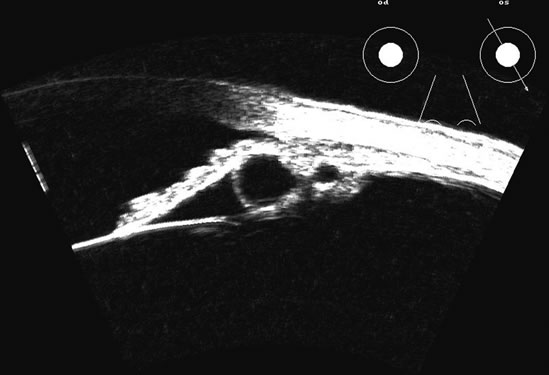

Fig. 17. This patient with a Molteno tube was treated for glaucoma. The top 50 MHz B-scan clearly shows the Molteno Tube (arrow). The bottom 10 MHz B-scan of the same patient demonstrates a choroidal detachment (large arrow) with associated posterior retinal detachment (small arrow). Choroidal elevations are typically convex, highly reflective surfaces with posterior limitation at the vortex vessels. Retina will always attach at the optic nerve. Choroidal elevations are often noted in several quadrants, as seen here.

The choroid, like the retina, is highly reflective and may resemble the retina when detached. Its thickness, which includes the retina, Bruch's membrane, and the choriocapillaris (tunica ruyschiana) is not usually differentiable when measured with routine ultrasound;12 however, it may be measured with digital techniques.18 Anatomically, the choroidal elevation is usually a smoothly round, convex surface, limited posteriorly by the vortex veins and anteriorly at any point up to the base of the iris (Fig. 17). The choroidal space should be examined for echoes (blood) or a clear zone, as seen with effusion or the serous part of a hemorrhage. In evaluating membranes from retina or choroid, it is always helpful to repeat the examinations at a later time.